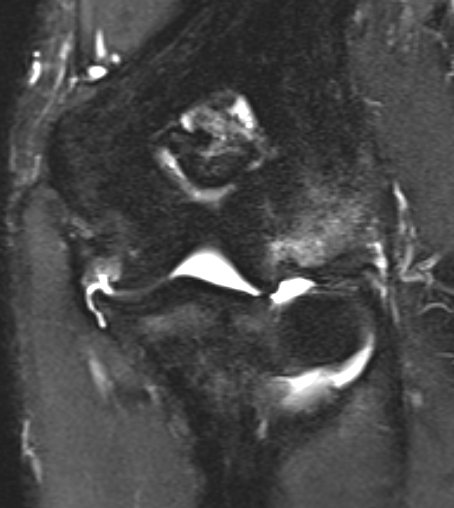

MRI

Intact

Grading of tears

Proximal / midsubstance / distal injury

Partial tears - low grade versus high grade

Complete tears

Acute full thickness UCL tear

High grade partial distal UCL tear

Bony avulsion UCL complex medial epicondyle

Bony avulsion UCL sublime tubercle